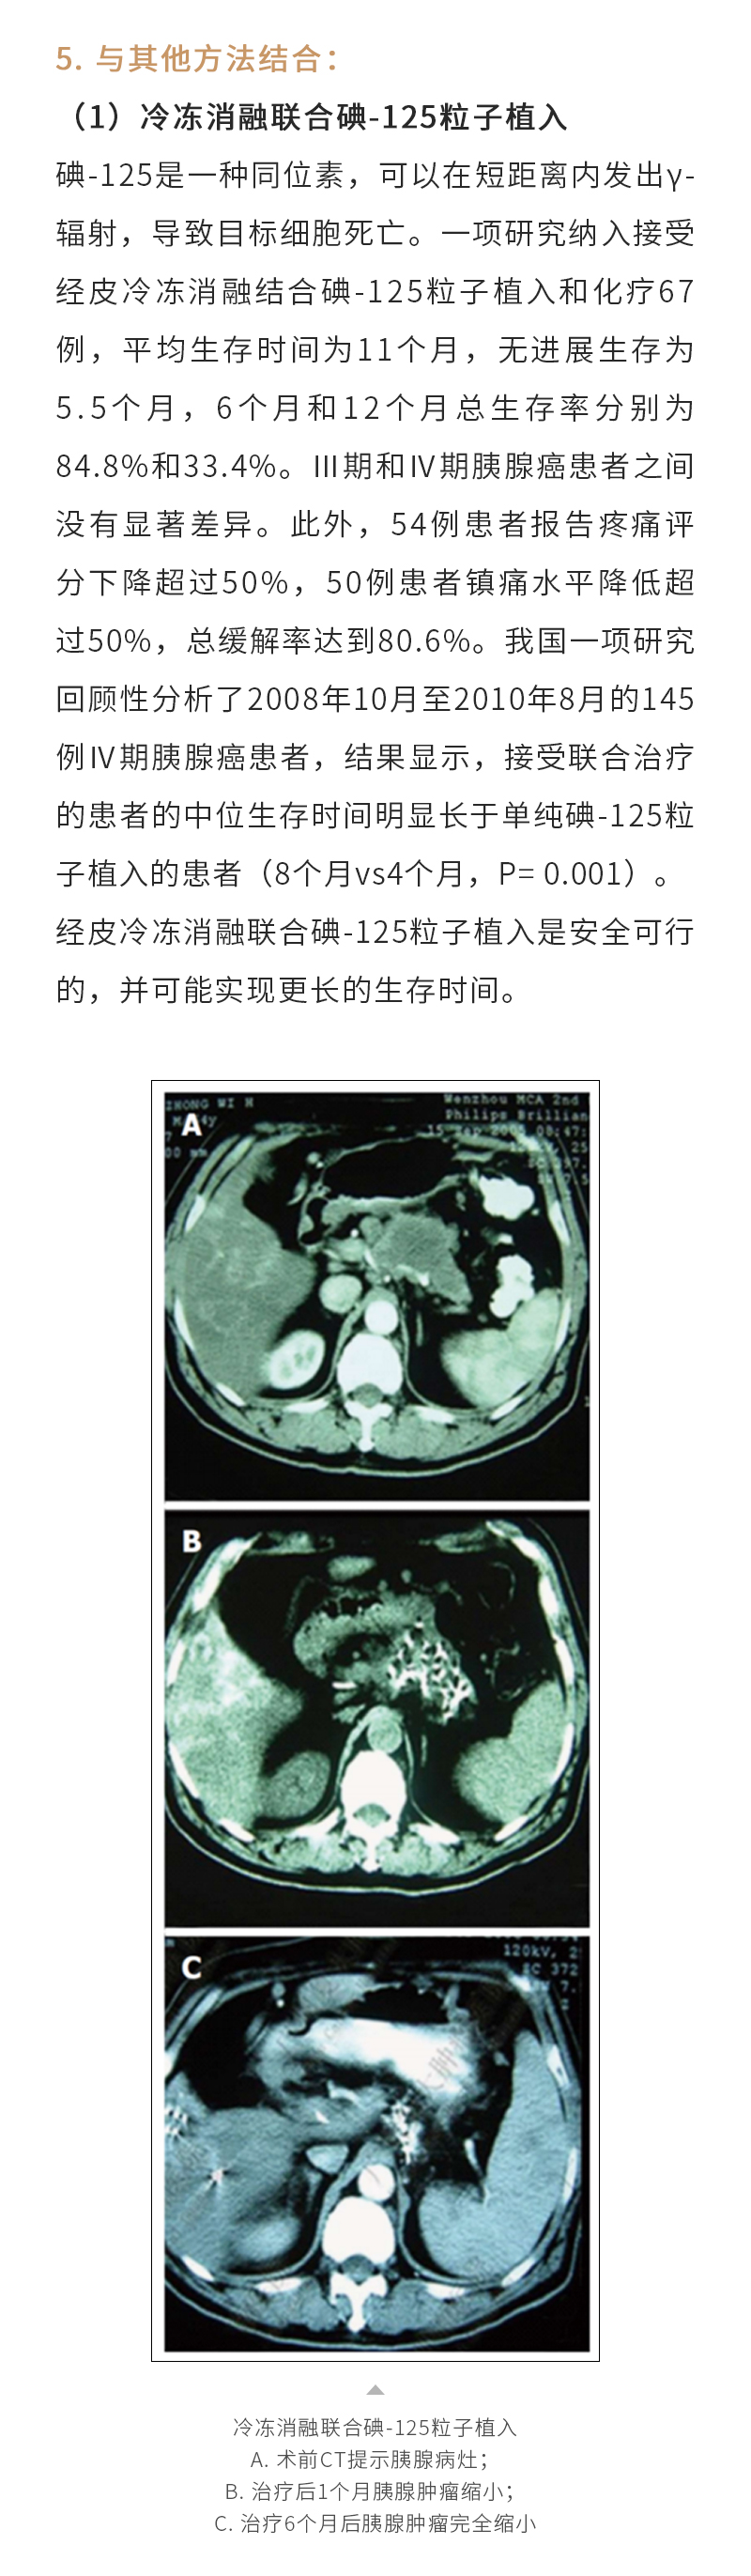

冷凍消融治療多種實(shí)體腫瘤——【海杰亞科研資訊】第257期